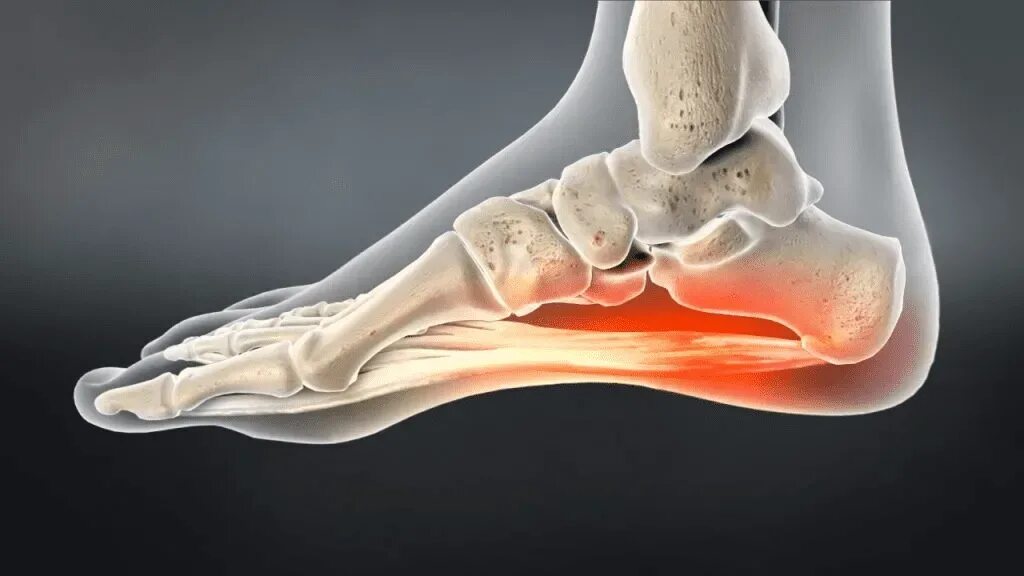

Пяточный фасцит